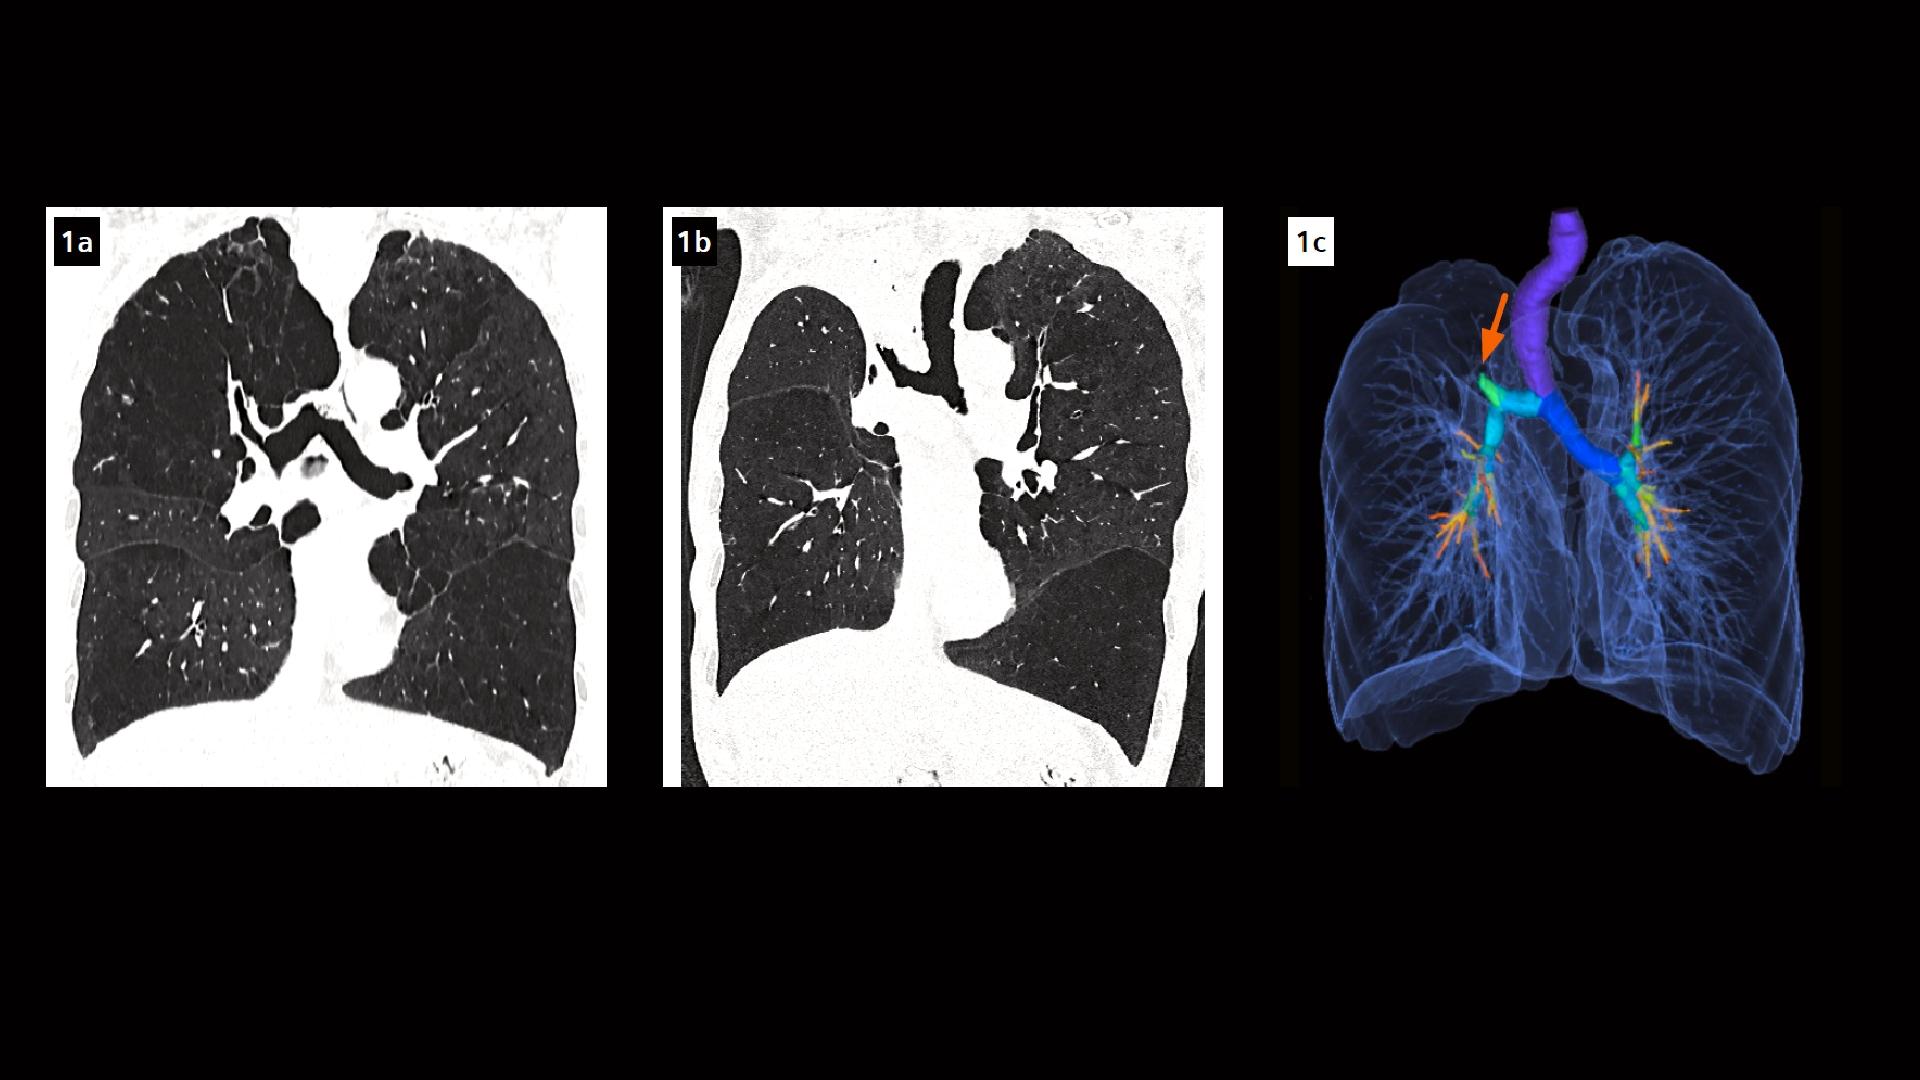

(a) Pneumothorax 1 day after treatment with endobronchial valves in

(a) Pneumothorax 1 day after treatment with endobronchial valves in Valves For Emphysema The zephyr valve is a device that can improve breathing in people with emphysema, one of the two most common types of chronic obstructive pulmonary disease (copd). During exhalation, the valves open, allowing air and other secretions to escape from the treated lobe. Food and drug administration today approved a new device, the zephyr endobronchial valve (zephyr valve), intended to. Valves For Emphysema.